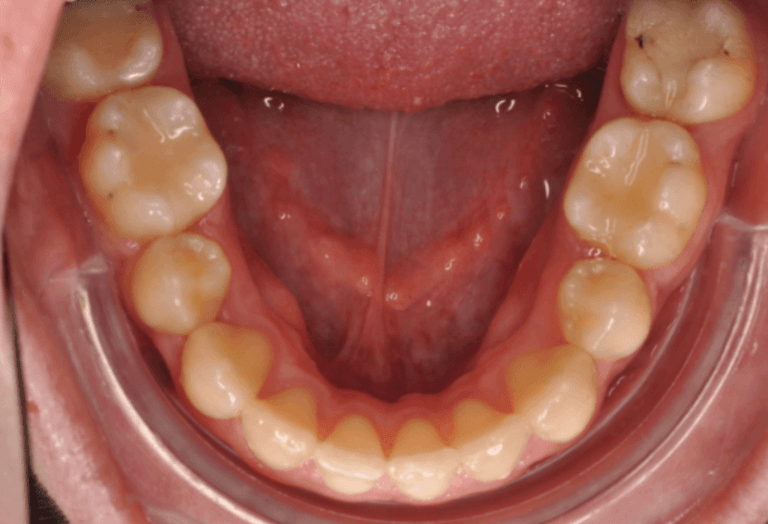

Kako slike obično govore više od reči, na sledećim slikama možete pogledati sjajne rezultate postignute nošenjem fiksnih proteza kod jednog našeg pacijenta: